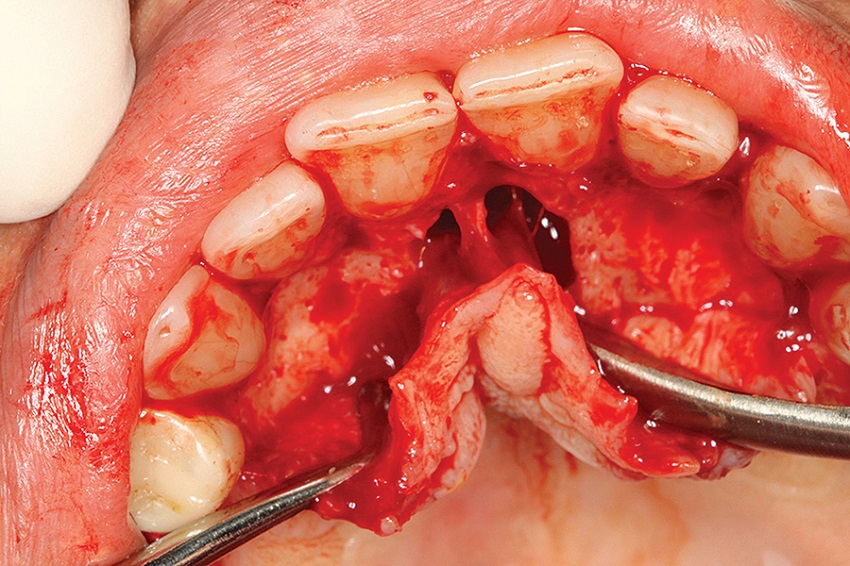

A 62-year-old male patient, Caucasian, sought the Stomatology Clinic of the Department of Dentistry of the Pontifícia Universidade Católica de Minas Gerais (PUC Minas) complaining of swelling in the anterior region of the palate. He reported realizing the condition 40 days before, which was continuously growing and painful to touch and when chewing. The anamnesis did not reveal systemic alterations. At extraoral examination, no alterations were observed. The intraoral examination showed a soft texture swelling, slightly purplish in color, with increased in translucency, suggestive of fluid content, covered by an intact mucosa, located on the anterior hard palate in the midline, close to the incisive papilla, measuring approximately 1.5 cm in diameter (Figure 1). Periapical and occlusal maxillary radiographs showed a well-defined unilocular radiolucent area in the incisive foramen region (Figure 2). Cone Beam computed tomography (CT) examination was requested to better evaluate the limits of the lesion, which showed a well-defined hypodense area, in continuity with the incisor canal, measuring 15 × 13 mm, in transversal and axial sections (Figure 3). Pulp vitality tests were performed on upper incisor teeth with a positive result for all of them. Based on the clinical and imaging characteristics, the diagnostic hypothesis of nasopalatine duct cyst was established, and the proposed treatment was surgical removal of the lesion. Under local anesthesia, aspiration of the lesion fluid was performed, which revealed the presence of translucent fluid. Subsequently, an intrasulcular incision and detachment of the palatal mucosa were performed in the region between the maxillary right and left first premolars (Figure 4). After exposure of the lesion, we performed dissection between the cystic capsule and the mucosa, which were adhered, followed by cyst enucleation and cleaning the surgical cavity (Figure 5). The mucoperiosteal flap was then repositioned and sutured.

A 25-year-old male patient attended the Stomatology Clinic of the Department of Dentistry of the PUC Minas complaining of a painful swelling in the central region of the hard palate, with three weeks of evolution time. The patient did not present noteworthy systemic alterations. The extraoral examination showed no alterations. In the intraoral examination, we observed the presence of a nodule in the central region of the hard palate, with a soft texture, covered by preserved mucosa and normal coloring (Figure 10). The maxillary occlusal radiograph showed a unilocular radiolucent well-defined lesion, in the anterior region of the maxilla, measuring about 3 cm (Figure 11). Tests of pulp vitality of the teeth close to the lesion were performed to rule out the possibility of inflammatory lesions of endodontic origin. The results were positive, and the diagnostic hypothesis was nasopalatine duct cyst. Under local anesthesia, aspiration of the lesion fluid (positive for translucent fluid) and excisional biopsy were performed, following a surgical protocol similar to the previously reported case (Figures 12 and 13). The material was sent for anatomopathological examination (Figure 14). The histological sections, stained with HE, showed cystic cavity covered by non-keratinized stratified squamous epithelia and fibrous connective tissue capsule with neurovascular bundles, confirming the diagnosis of NPDC.